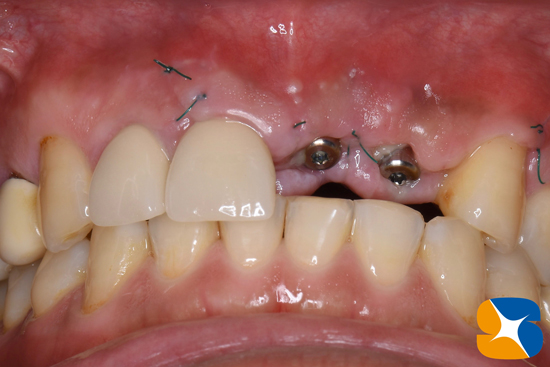

テレビ関係者のため、直ぐにでも前歯が必要でしたので、施術後1週間で型取りを行いました。

※傷口を縫い合わせる糸はまだ残ったままの状態

施術後、僅か2週間で仮のインプラントを装着しました。